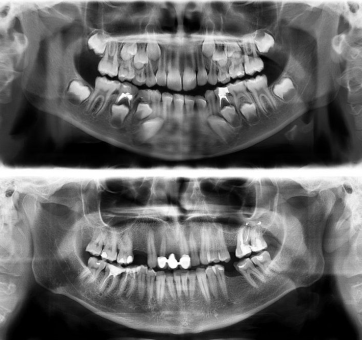

A radiografia dentária é dividida em dois tipos.

A radiografia intrabucal, que é realizada na parte interior da boca, e a extrabucal que é realizada na parte exterior da boca.

Radiografia intrabucal: o exame radiográfico realizado dentro da boca pode ser interproximal, periapical ou oclusal. O exame interproximal, também conhecido como bitewing, visa conhecer a mordida do paciente de forma detalhada. Dessa maneira, é possível identificar a presença de cáries, por exemplo. O exame periapical tem como foco o reconhecimento do dente por completo, incluindo a coroa dentária e seu osso de sustentação. Já o exame oclusal possibilita que o profissional observe o assoalho bucal. Assim, o profissional da odontologia consegue enxergar melhor a mordida a partir de cima.

Radiografia Extrabucais: